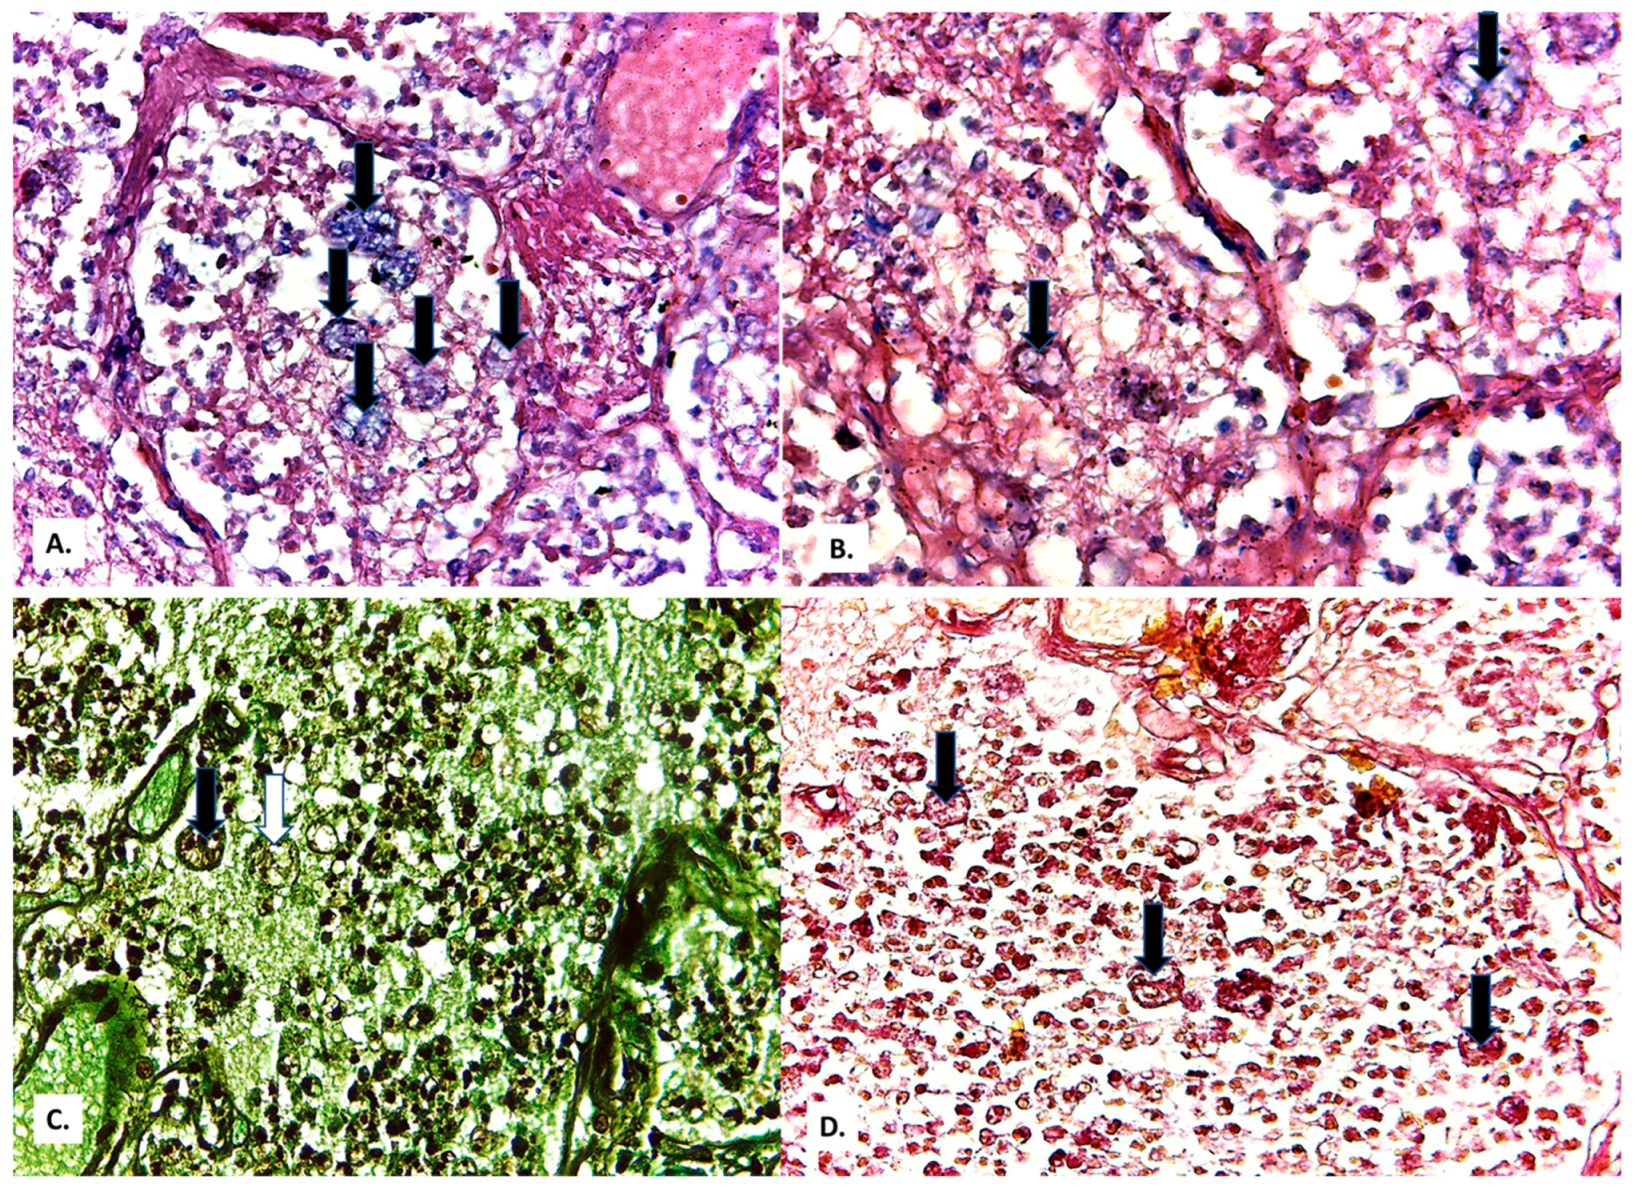

2. Case Presentation